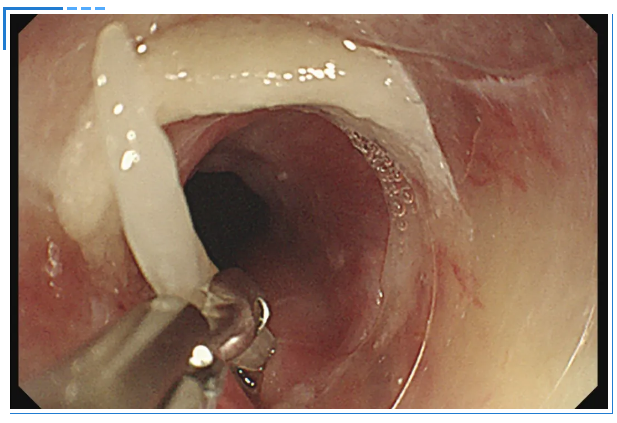

这时,消化内科主任吕后宁大夫有了一个大胆的想法:对透明帽进行改良。说干就干,吕主任迅速行动起来。他利用现有材料,经过一番巧妙的改造,一个特制的内镜透明帽应运而生。这个小小的豁口,就像是在透明帽上打开了一个“操作窗口”,为异物钳的操作预留了空间。

一切准备就绪后,医生再次为陈女士进行内镜操作。胃镜带着改良后的透明帽缓缓进入食管入口,当鱼刺出现在视野中时,吕主任轻轻旋转胃镜角度,将透明帽的豁口精准对准鱼刺嵌顿的位置。随后缓慢推送胃镜,让鱼刺的一部分稳稳地进入豁口内——此时豁口如同一个“固定卡槽”,将鱼刺牢牢固定住。

紧接着,异物钳从内镜通道中缓缓伸出,借助豁口提供的充足空间,异物钳以最佳角度顺利接近鱼刺,精准地夹住了鱼刺。医生确认夹持牢固后,保持异物钳与胃镜轴线平行,缓慢退镜。退镜过程中,透明帽始终包裹着鱼刺,有效避免了鱼刺尖端划伤食管壁。当胃镜退出口腔时,那根让陈女士痛苦不已的鱼刺被完整取出。